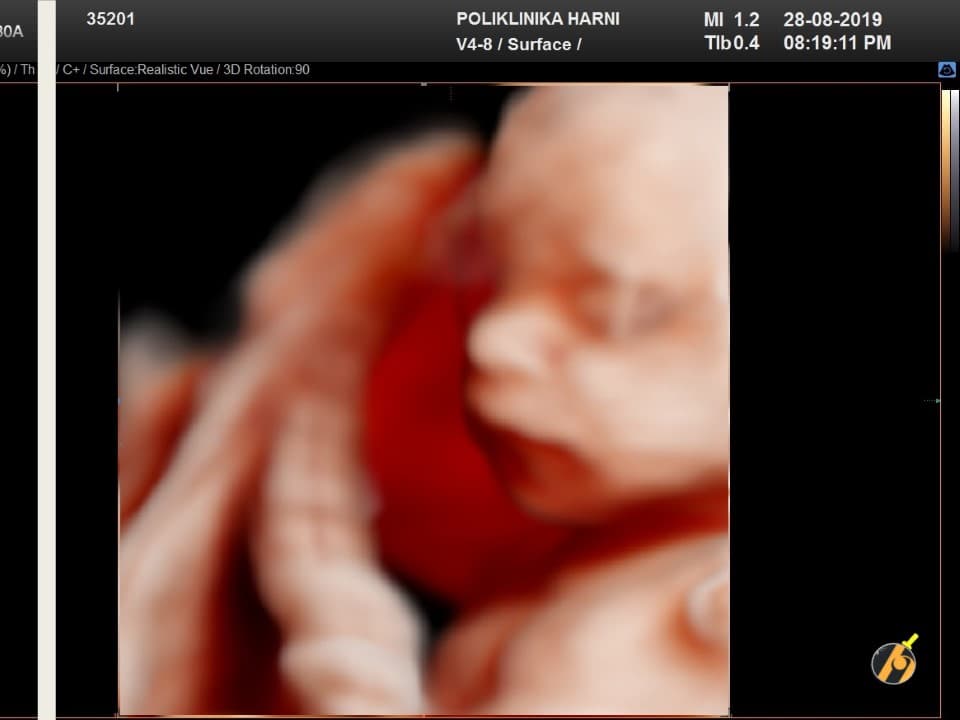

Oko 20. tjedna trudnoće obično se obavlja detaljan ultrazvučni pregled drugog tromjesečja, poznat kao morfološki ultrazvuk ili anomaly scan. Tijekom tog pregleda procjenjuju se razvoj i anatomija fetusa, razvoj mozga, srca i drugih organa, količina plodove vode te položaj i izgled posteljice.

Ovaj pregled omogućuje liječniku da procijeni razvija li se beba uredno te pruža važan uvid u tijek trudnoće, kao i da preporuči dodatne pretrage kao što su fetalna neurosonografija ili fetalna ehokardiografija.